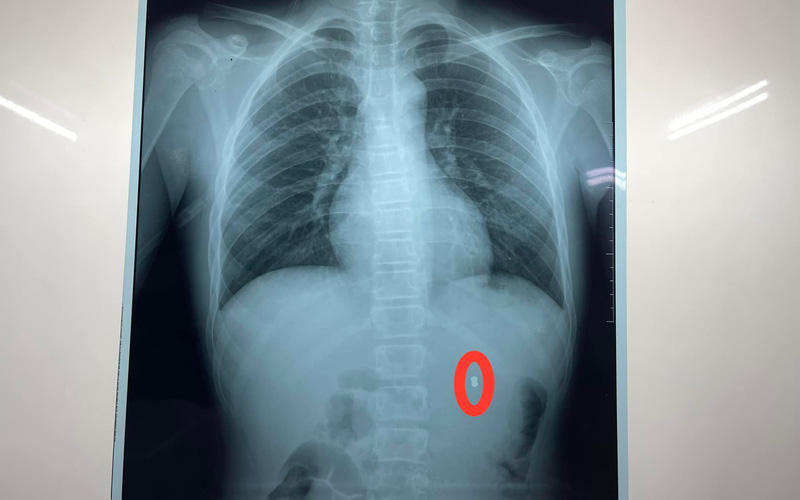

Sau khi được siêu âm, chụp CT bụng có cản quang, phát hiện dị vật hình viên đạn trong thận trái, bệnh nhân được chuyển đến Khoa Ngoại thận tiết niệu nam học. Các bác sĩ đã nhanh chóng hội chẩn và kết luận: bệnh nhân có vết thương thận trái cho đạn bắn, chỉ định mổ cấp cứu lấy dị vật và khâu bảo tồn thận.

Ê-kíp phẫu thuật đã thực hiện rạch vết thương thận, lấy viên đạn súng hơi ra ngoài, khâu cầm máu vết thương, làm sạch khoang quang thận, đồng thời, truyền 500ml máu trong cả quá trình phẫu thuật. Ca phẫu thuật diễn ra thành công sau 1 giờ đồng hồ, đầu đạn chì kích thước 0,4×0,7cm đã được lấy ra ngoài.